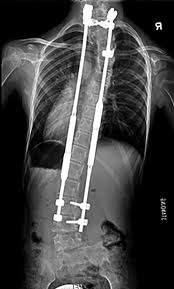

Yapılan bir araştırmaya göre, omurgaya yerleştirilen ve çocuk büyüdükçe dışarıdan mıknatıs yardımıyla ayarlanabilen özel destek çubukları, 1. tip SMA hastası olan çocuklarda omurga eğriliğini kontrol altına almada işe yarayabilir. Araştırmacılar, manyetik çubuk yönteminin SMA hastaları için hem güvenli hem de faydalı göründüğünü söylüyor.

Çalışmada İtalya’da tedavi edilen 8 çocuk incelendi. Bu çocukların yaşları 5 ile 8 arasındaydı. Hepsinde omurgada belirgin eğrilik vardı ve hepsine aynı tür ameliyat uygulandı. Bu yöntemde omurganın yanına destek çubukları yerleştiriliyor. Çocuk büyüdükçe bu çubuklar yeniden büyük bir ameliyat yapmadan, mıknatıs yardımıyla ayarlanabiliyor. Benzer amaçla kullanılan bazı eski yöntemlerde çocuk büyüdükçe yeni ameliyatlar gerekebiliyor. Burada ise ayarlama işlemi daha pratik yapılabiliyor.

Omurgadaki eğriliğin derecesine bakıldığında belirgin bir düzelme görüldü. Ölçümlere göre ortalama eğrilik seviyesi 71,9 dereceden 38,9 dereceye indi. Bu da yaklaşık yüzde 46’lık bir iyileşmeye işaret ediyor. Takip sürecinde eğrilik biraz artsa da, başlangıç durumuna göre yine daha iyi seviyede kaldı.